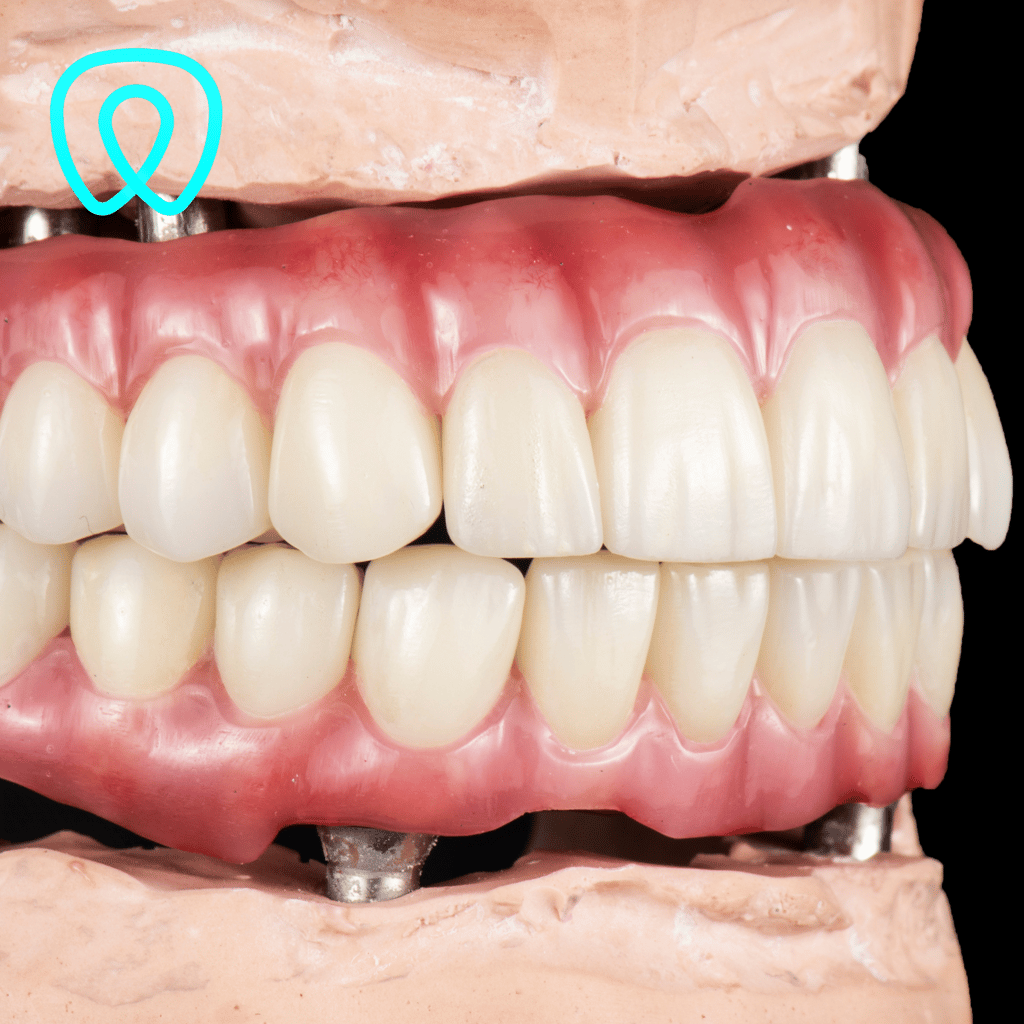

Diseñamos prótesis completas que sustituyen todos los dientes perdidos, mejorando la estética y funcionalidad de tu boca, o prótesis parciales removibles para pacientes que han perdido varios dientes. Nuestras prótesis son personalizadas para garantizar comodidad y un ajuste ideal.

Prótesis dental

Sobredentadura

Las sobredentaduras son una excelente opción para pacientes con pérdida total de dientes. Estas prótesis se fijan sobre implantes dentales, ofreciendo mayor estabilidad, comodidad y confianza al hablar y comer. Incluso ahora podemos realizarlas con implantes subperiósticos para pacientes que antes no se podían rehabilitar.